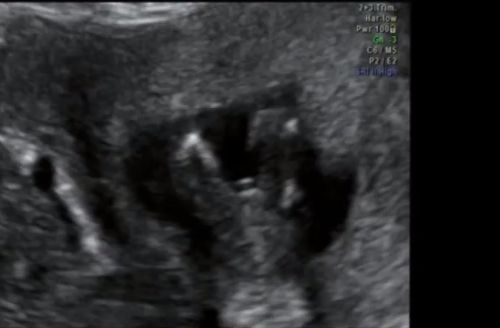

I'd prepare for a boy. I don't see a hamburger below that, and I doubt it's just a cord.

Looks like my little man's potty shot - that 'hotdog' is going nowhere! Congrats!